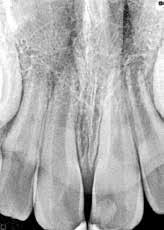

Fig. 1. A. Udsnit af panoramaoptagelse viser Ca(OH)2 uden for foramen apicale i en overkæbemolar og i sinus maxillaris (pil). B. Periapikal optagelse viser Ca(OH)2 uden for foramen apicale (pil) i en central incisiv. Tilfældet krævede kirurgisk indgreb.

Fig. 1 A. An orthopantomography section showing Ca(OH)2 beyond the apical foramen of maxillary first into the maxillary sinus (arrow) and (B) a periapical radiograph with Ca(OH)2 extrusion beyond the apical foramen (arrow) of a central incisor which required surgical intervention.

Ved mistanke om malpraksis vurderer man behandlerens handlinger i alle stadier i relation til opgavens kompleksitet og tager stilling til, om disse lever op til normen for almindelig anerkendt faglig standard. De mest omfattende skadevirkninger ses i forbindelse med anvendelse af endodontiske skyllevæsker og andre medikamenter, fx ulykker med natriumhypoklorit eller skader på nervevæv eller i sinus som følge af udpresning af calciumhydroxid igennem foramen apicale (Fig. 1A og B) (5,6). Sådanne uheld vurderes ofte til at være undgåelige, idet tandlægen ikke har levet op til normal faglig standard. Frygt for at begå procedurefejl eller andre utilsigtede hændelser bør dog ikke få klinikeren til helt at afstå fra at foretage endodontiske behandlinger (7).